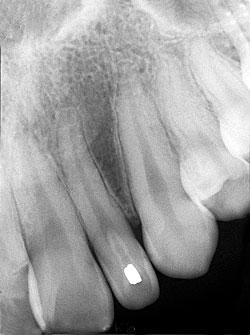

A 27-year-old male visited a dental office for a routine checkup. Radiographic examination revealed an unusual enamel-like radiopacity within the left maxillary lateral incisor.

A review of the periapical films revealed a small radiopacity within the crown of the left maxillary lateral incisor (see radiograph). Clinically, the lateral incisor appeared small and peg-shaped. No other abnormalities were noted on the radiographs.

The dens invaginatus typically appears as a pear-shaped invagination of enamel and dentin within the crown and/or root of the tooth that closely approximates the pulp cavity. This in-folding of enamel can be easily recognized on a dental radiograph by its increased radiopacity - it resembles the radiodensity of enamel seen on the external surface of the tooth. Radiographically, the dens invaginatus appears as a small tooth-like structure within the affected tooth. The dens invaginatus is often associated with a periapical radiolucency because of the high incidence of pulpal death and necrosis.